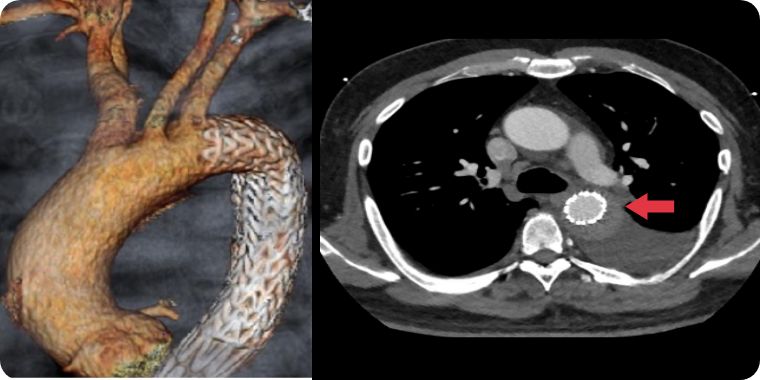

大動脈解離は、突然発症する疾患で、大動脈に亀裂が入り、血管が裂ける病気です。急性期には解離した血管壁が薄くなり、破裂を起こす可能性や主要臓器への血流が遮断されることで臓器障害を引き起こす可能性があります。治療法は、動脈瘤と同様に人工血管置換術とステントグラフト内挿術があり、病態に合わせて適切な治療を行います。

当院では大動脈解離の治療法にオープンステントグラフトを導入しています。オープンステントグラフトは広範囲の解離部分に対して治療効果が得られる利点があります。

解離した場合によっては、ステントグラフト治療が適応になることがあります。大動脈解離に対するステントグラフト治療は専門性が高く、心臓血管に特化した当院の大動脈専門スタッフが慎重に判断して施行しています。

白矢印が大動脈の亀裂、赤矢印はステントグラフトで亀裂を閉鎖していることを示す。